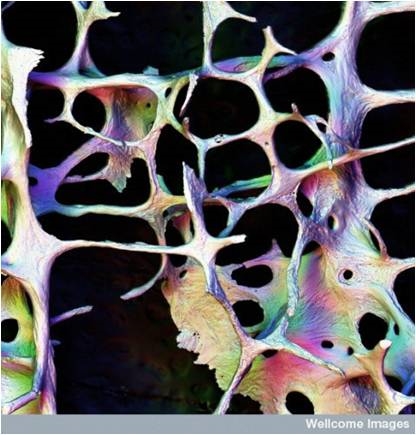

Osteoporosis y fracturas

La osteoporosis es una enfermedad crónica que requiere terapia a largo plazo. Del correcto tratamiento con medicamentos para prevenir la pérdida ósea y reducir el riesgo de fractura desempeña un papel importante en la gestión de la enfermedad y su evolución